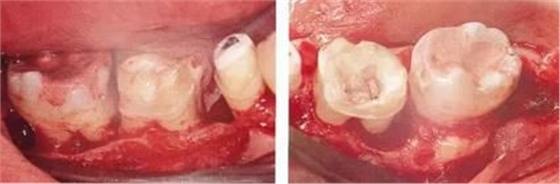

▲圖7-2,3

▲圖7-2 齦瓣剝離后,可以看到右上3近中側(cè)沉積著大量牙結(jié)石。由于牙根接近而無法用刮匙除去

▲圖7-3 牙周外科處理后的愈合期狀態(tài)。右上2,3之間愈合形成了充分的角化齦。